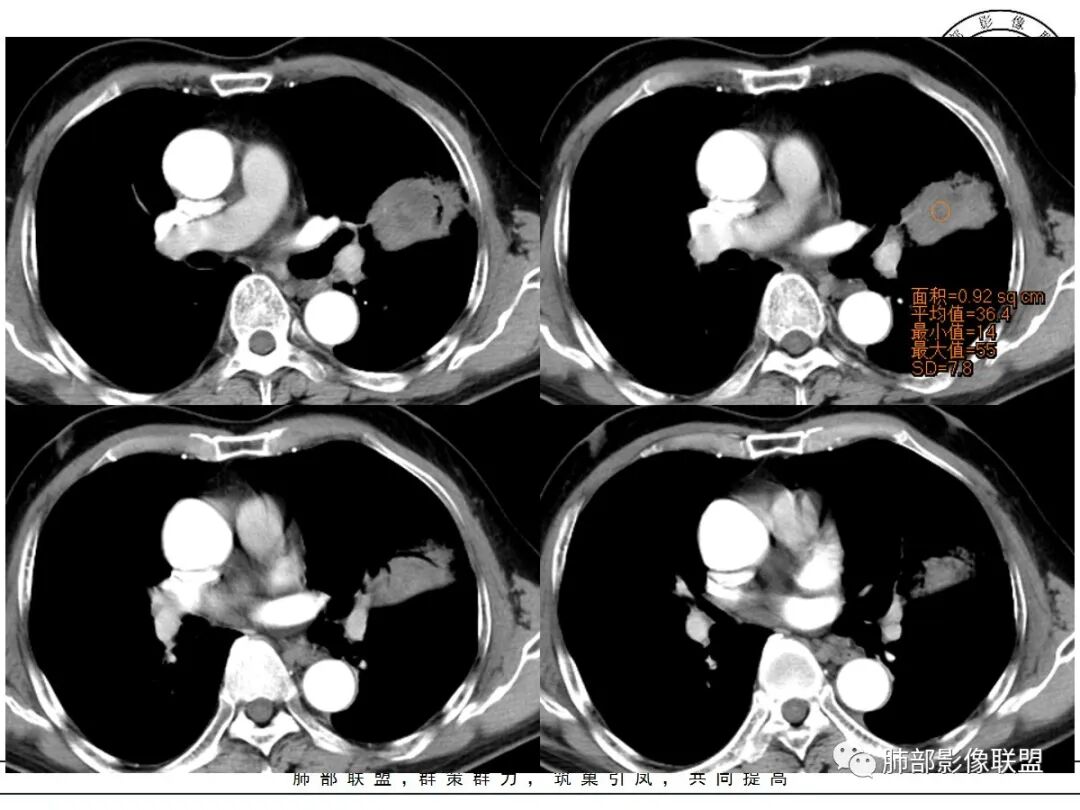

强化如何?

强化有疑问,前面感觉有低密度的,有些图好像又均匀

不均匀中度强化

不均匀轻中度渐进强化。

不均匀性强化,远端坏死比较明显

如果强化明确,那就可以排除曲菌球。

2、偏心空腔病灶,气腔略呈新月形,壁不规则,腔内结节相对密实,明显强化且不均,支持新生物而非曲菌球等。炎性空洞多有强化环。

3、病变强化较明显,其内隐约显示多发小斑片状无强化灶,可疑边界不清小灶坏死区。病灶内血管影浅淡、模糊不规则。